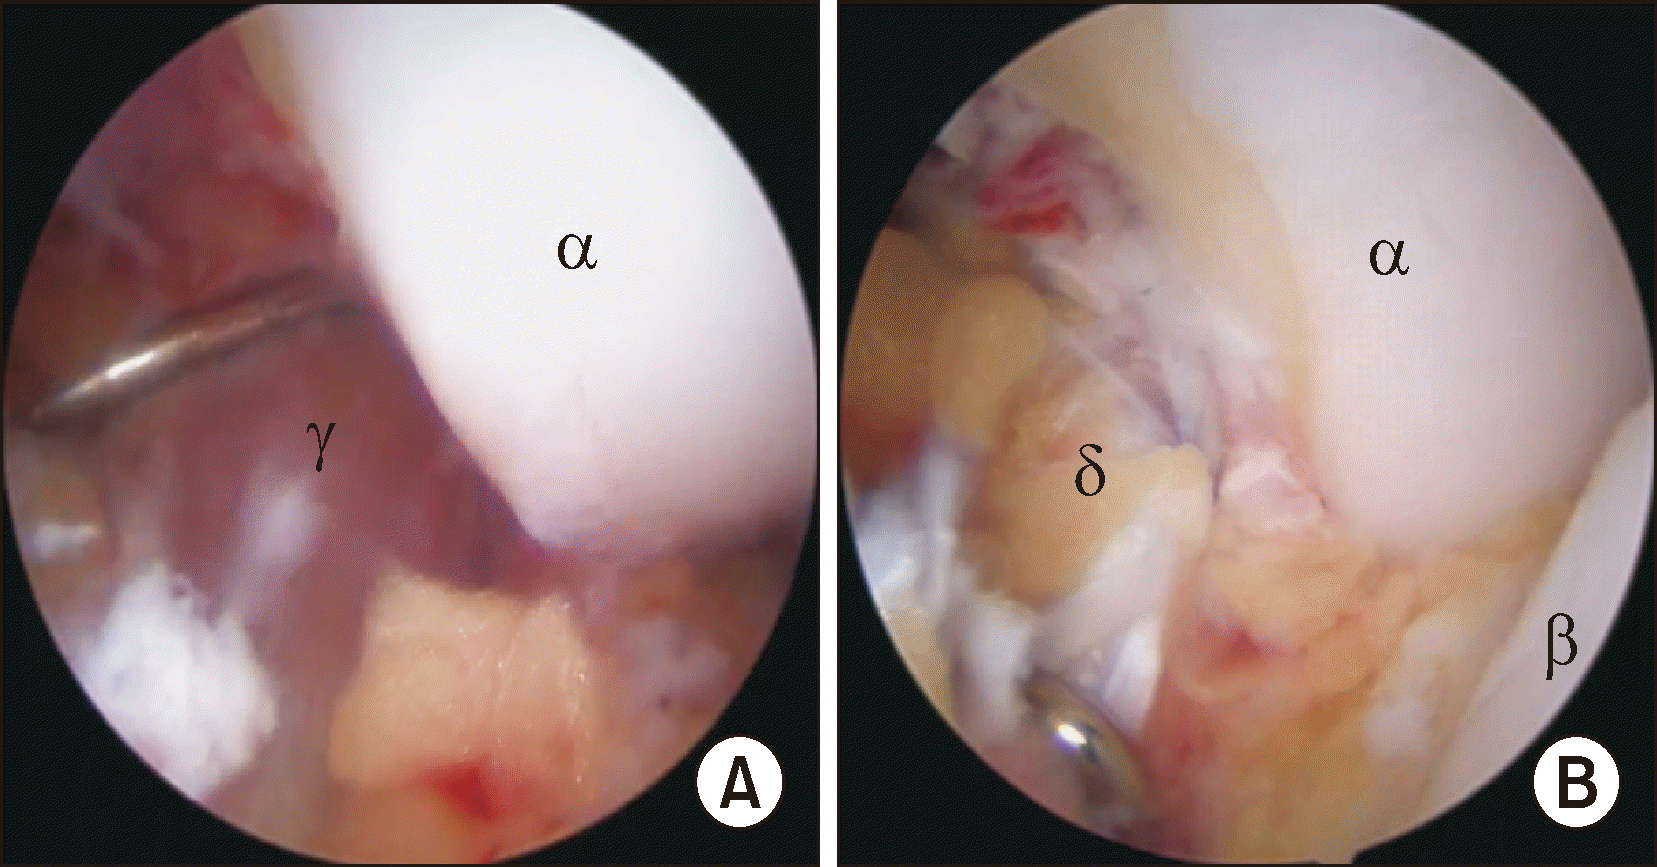

Figure 5

After identifying the deltoid ligament injury with an arthroscopic probe (A), the deltoid ligament is repaired with FiberWire and Knotless SutureTak Anchor (B). αTibia, βTalus, γInjured deltoid ligament, δRepaired deltoid ligament.

Figure 6

The arthroscopic findings show the medial malleolar fracture before (A) and after (B) arthroscopic reduction. αTibia, βTalus, γfractured medial malleolus.